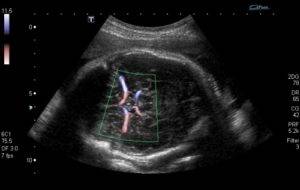

- триплексное сканирование: исследует кровоток и проходимость сосудов. Цвет будет зависеть не от вида сосуда или артерии, а от направления движения кровотока.

Как делают эту процедуру? Пациентка ложится на кушетку на левый бок или спину. Живот при исследовании должен быть открыт от лобка до груди. На живот женщине наносят специальный гель (каплю). По нему во время работы аппаратуры передвигается датчик УЗИ. На экране появится цветное изображение, где красный цвет будет показывать течение крови, которая устремлена в сторону датчика, а синим цветом показаны струи кровяной плазмы, идущие в обратном направлении. Более высокая интенсивность того или иного цвета указывает на повышение скорости кровотока.

Датчик с допплером визуализирует строение сосудов, интенсивность кровотока. Компьютер регистрирует изменение сигнала, данные обрабатываются в программе и выводятся на монитор. Диагностика подходит для венозного и артериального кровообращения мелких и крупных сосудов.

Современные аппараты УЗ-диагностики дополняются допплерометрическими функциями, поэтому обследование проводится параллельно с плановым осмотром и занимает в среднем 10 минут. Доктор изучает расположение сосудов, затем смотрит на интенсивность кровотока. Режим допплерографа дает изображение на монитор с аппаратной оценкой параметров. Диагностика выполняется в следующих режимах:

Первый вариант предусматривает изучение проходимости сосуда, поиска изменений скорости потока крови. Второй тип обследования, помимо предыдущих функций, включает цветовое картирование. На экране видна скорость кровотока в контрастном изображении, что дает больше возможностей в плане диагностирования сосудистой патологии. К преимуществам допплерографии можно отнести: